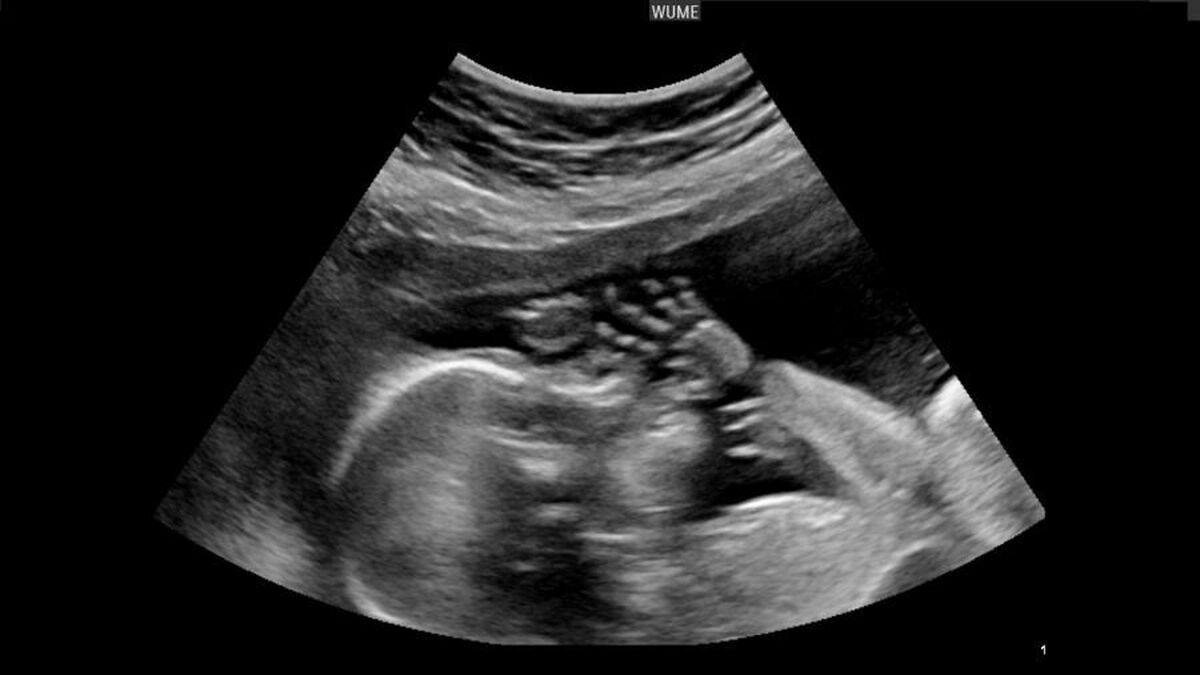

سقط عمدی جنین، از نظر شرعی و قانونی، ممنوع است؛ مگر در موارد استثنایی که در ماده ۵۶ «قانون حمایت از خانواده و جوانی جمعیت» بهصراحت پیشبینی شده باشد.

بر اساس این ماده قانونی، صدور مجوز سقط جنین تنها در صورت احراز شش شرط ممکن است:

رضایت مادر

وجود حرج (مشقت شدید و غیرقابل تحمل) برای مادر

وجود قطعی ناهنجاریهای جنینی غیرقابل درمان در مواردی که منشأ حرج، بیماری یا نقص جنین باشد

عدم امکان جبران و جایگزینی برای حرج مادر

نبود نشانههای ولوج روح

کمتر بودن سن جنین از چهارماه